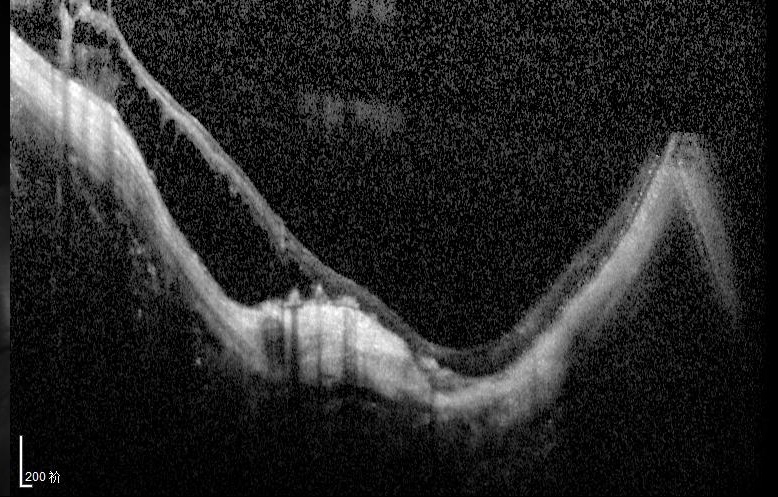

我检查以后发现他双眼的裸眼视力都非常差,右眼只有50公分数指,左眼只有0.02,矫正视力右眼戴2000度眼镜勉勉强强可以看0.05,左眼戴1900度眼镜也只能勉勉强强看到0.15,双眼晶状体轻度浑浊,玻璃体浑浊。最令我吃惊的是老人家双眼黄斑区视网膜不仅萎缩得像一张薄纸,而且还有劈裂性脱离及视网膜下陈旧性疤痕形成。

右眼手术以前眼底(萎缩、劈裂性脱离及视网膜下陈旧性疤痕)

左眼手术以前底(萎缩、劈裂性脱离及视网膜下陈旧性疤痕)